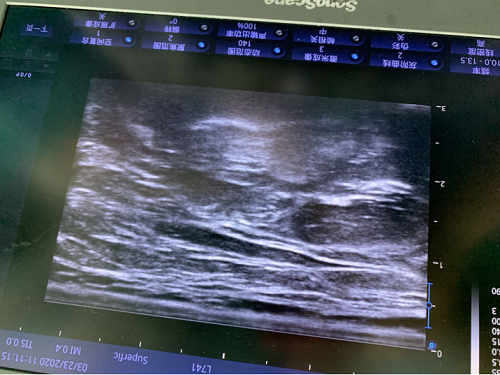

2020年3月9日,涪陵区人民医院麻醉科在一例左肱骨下段骨折切开复位内固定术中首次应用超声技术进行超声引导下臂丛神经阻滞麻醉并取得成功。

这是一例中年男性病例,选用臂丛神经阻滞麻醉应用于上肢手术,传统上使用解剖定位的方法,但这是盲探性的麻醉操作,容易发生神经阻滞不全并增加并发症的危险。超声技术的运用,有效弥补了传统方法的缺陷,关键是能准确定位神经,能更好观察局部药物扩散的情况,有效提高臂丛神经阻滞麻醉成功率,实现精准麻醉的定义。超声技术应用,不仅是在本例病例中体现优势,还积极应用于围术期管理,包括经颅多普勒监测、超声引导下深静脉穿刺置管和经食管超声心动图。超声技术的应用也对医院麻醉科提出更高技术的要求,麻醉医生需要掌握的超声技术涉及全身多个系统,主要围绕临床麻醉工作中最重要的气道、呼吸、循环、神经等多个方面展开。

本次超声技术的成功开展,使神经阻滞能确保局部组织的针对性与有效性,是医院麻醉将超声技术紧密临床麻醉工作的第一步,标志着医院麻醉科超声引导下神经阻滞技术迈上一个新台阶。